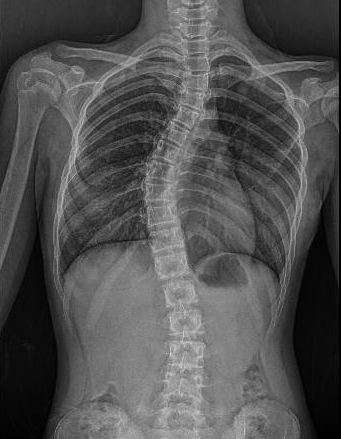

Scoliosis is defined as an abnormal lateral curvature of the spine, often accompanied by vertebral rotation. Most cases are diagnosed during adolescence, and severity varies – from mild asymmetry to curvatures exceeding 45 degrees that require surgical correction.

According to Dr Tan Jin Aun, Consultant Orthopaedic and Spine Surgeon at SMCD, patients with mild scoliosis (typically between 20 and 40 degrees) often remain asymptomatic aside from visible postural differences. “Secondary health effects tend to occur when curvature becomes severe, generally between 70 to 100 degrees,” Dr Tan explains. “At this stage, the impact can vary depending on several factors of which include the age and overall health of the patient. The location of the curve and the type of scoliosis also influence whether respiratory or digestive complications arise.”

As scoliosis progresses, it can begin to influence key physiological functions – starting with two of the most commonly affected areas: breathing and digestion. When the spine curves abnormally, it can rotate or twist the ribcage. This reduces lung volume and causes restrictive lung disease, making it harder for patients to breathe deeply. “For thoracic curves, an angle of 70 degrees or more may start limiting lung expansion while a curve of more than 100 degrees can lead to severe pulmonary restriction and thus, difficulty in breathing or decreased effort tolerance,” says Dr Tan. Similarly, severe deformity (such as lumbar curves above 90 degrees) can compress the abdominal cavity which may lead to bloating, acid reflux, or constipation – symptoms that can be commonly misattributed to gastrointestinal issues.